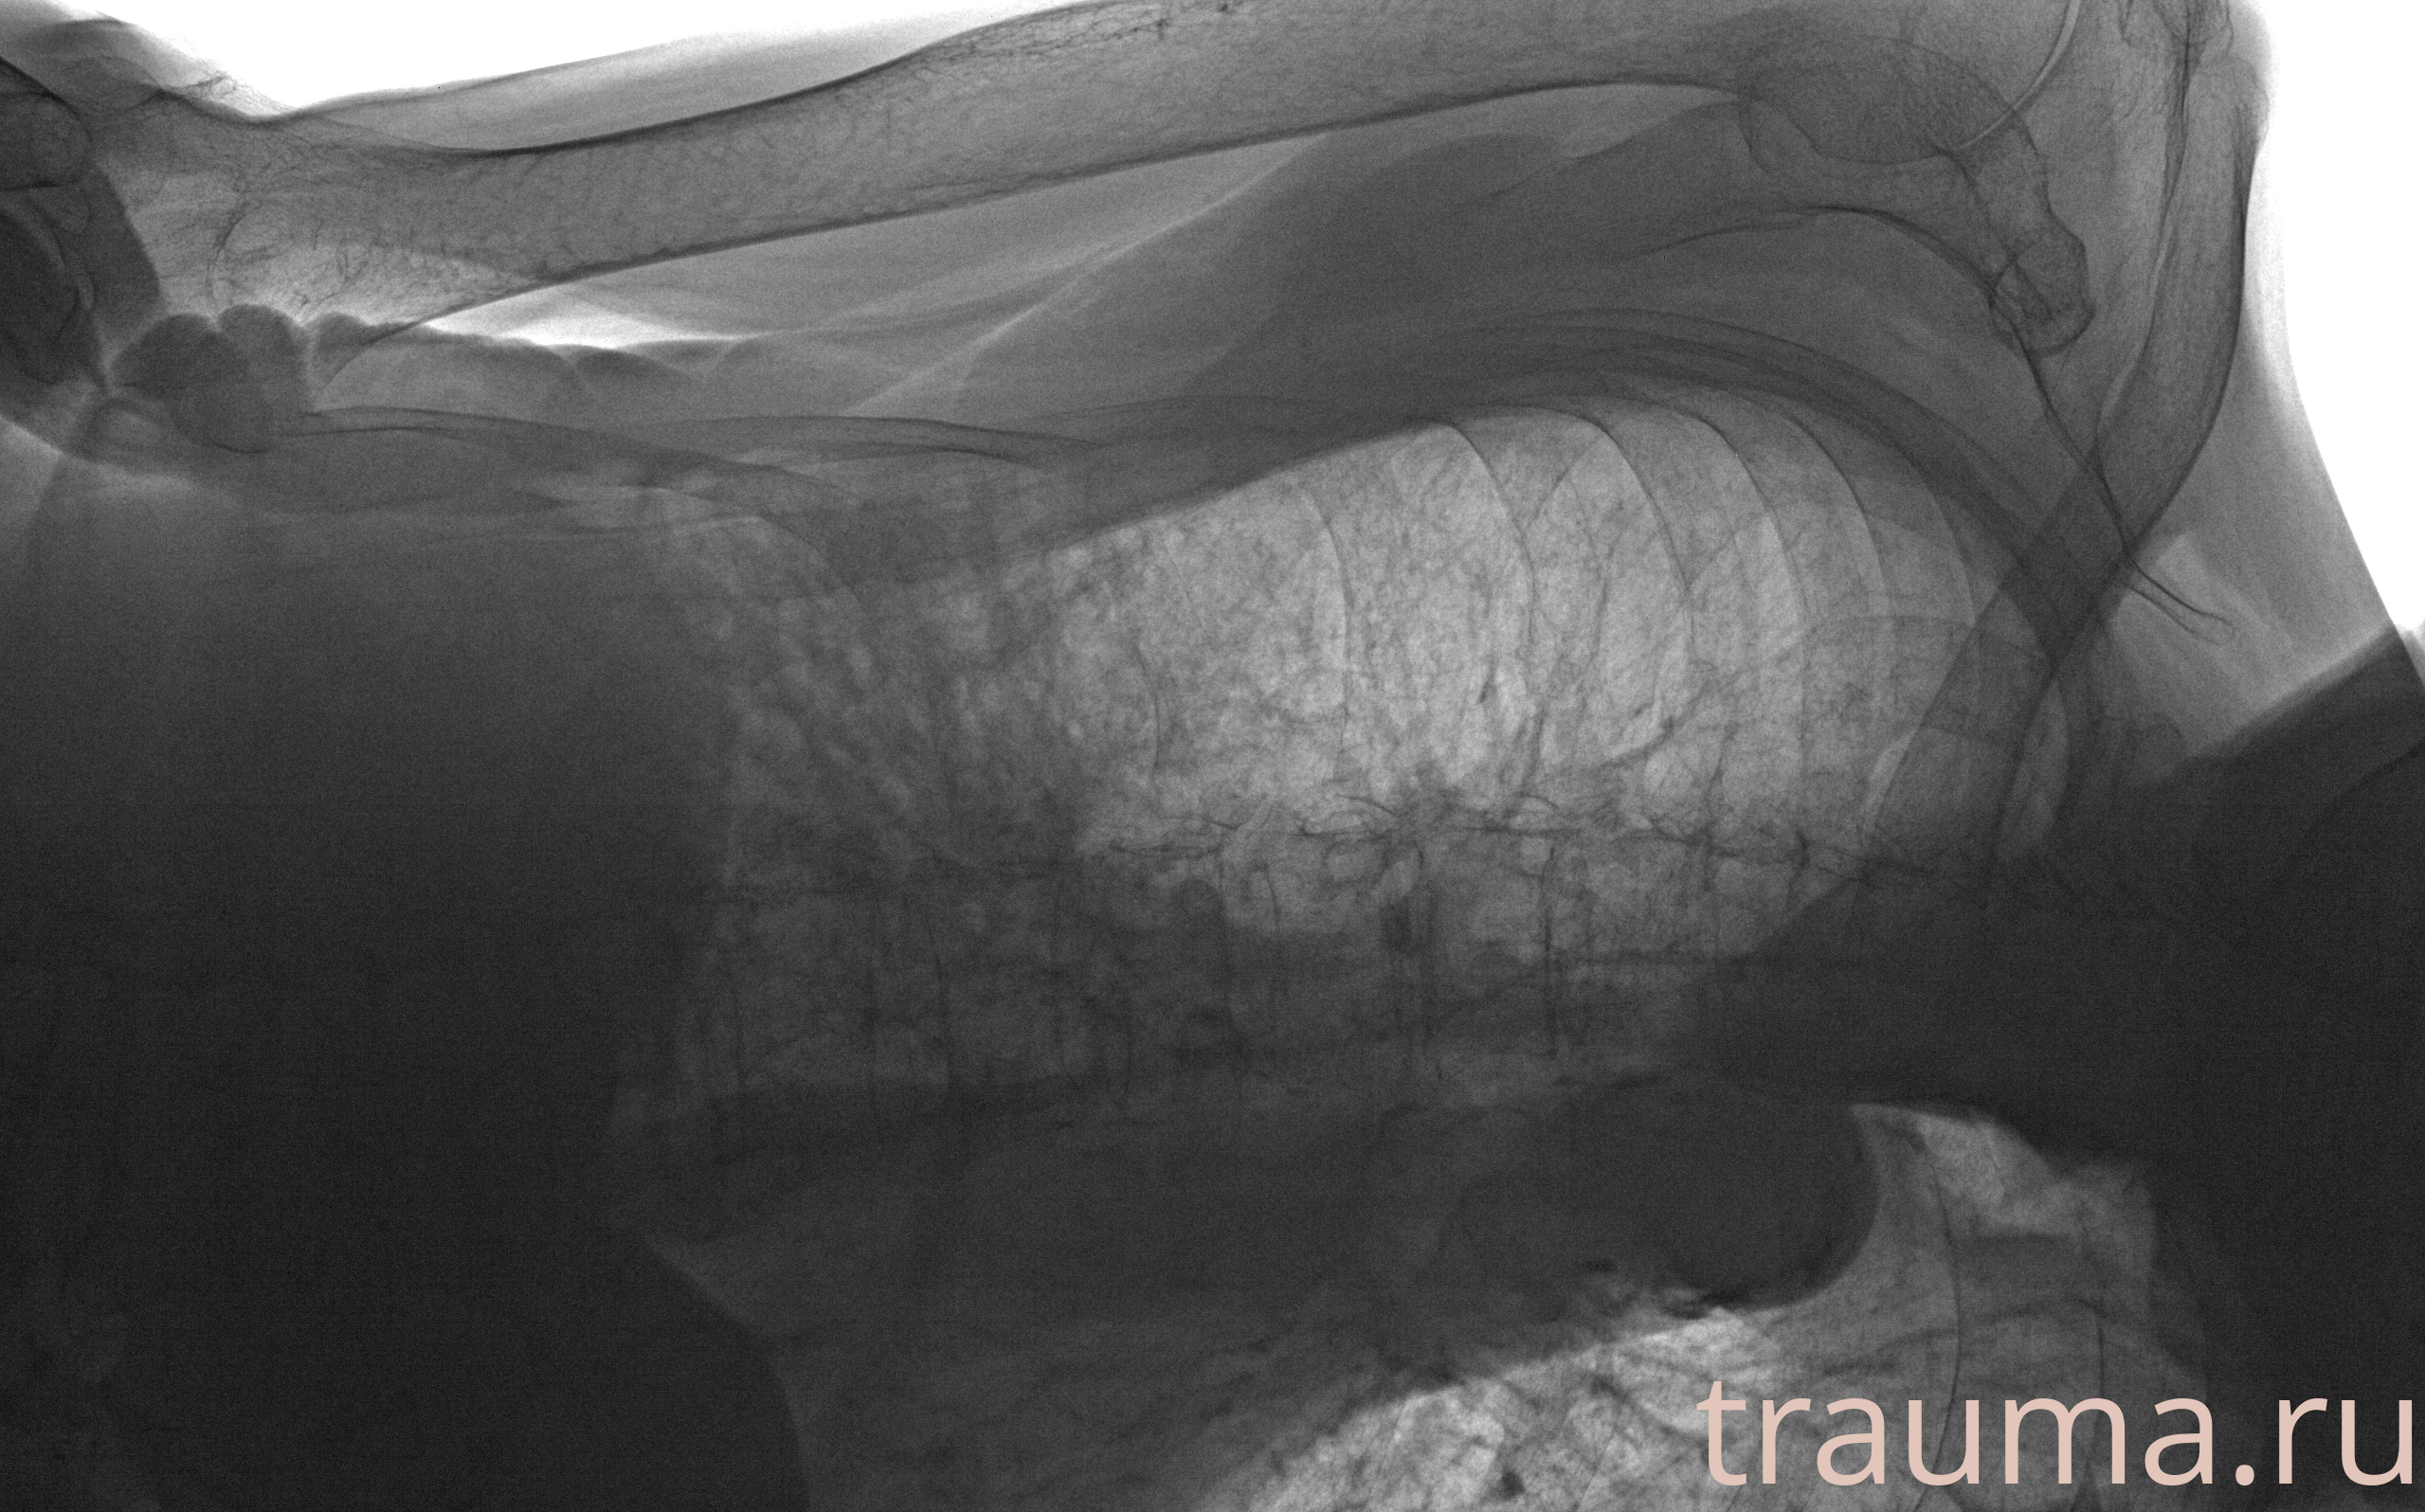

Рентгенограммы

Рентген на дому: по вашему адресу приезжает врач-рентгенолог, травматолог-ортопед с мобильным рентгеновским аппаратом, проводит диагностику травмы или заболевания, делает необходимые рентгенограммы, дает рекомендации по дальнейшему лечению. Получить качественные снимки в домашних условиях возможно благодаря уникальной методике, разработанной МосРентген Центром для института  Склифосовского